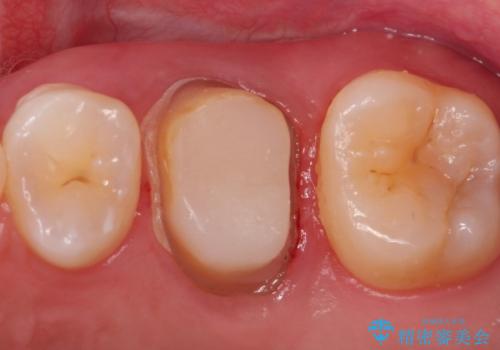

大きい虫歯 根管治療〜オールセラミッククラウン

- 歯が欠けたことを主訴に来院されました。

再根管治療後、歯周外科を行い、オールセラミッククラウンにて修復処置を行っております。